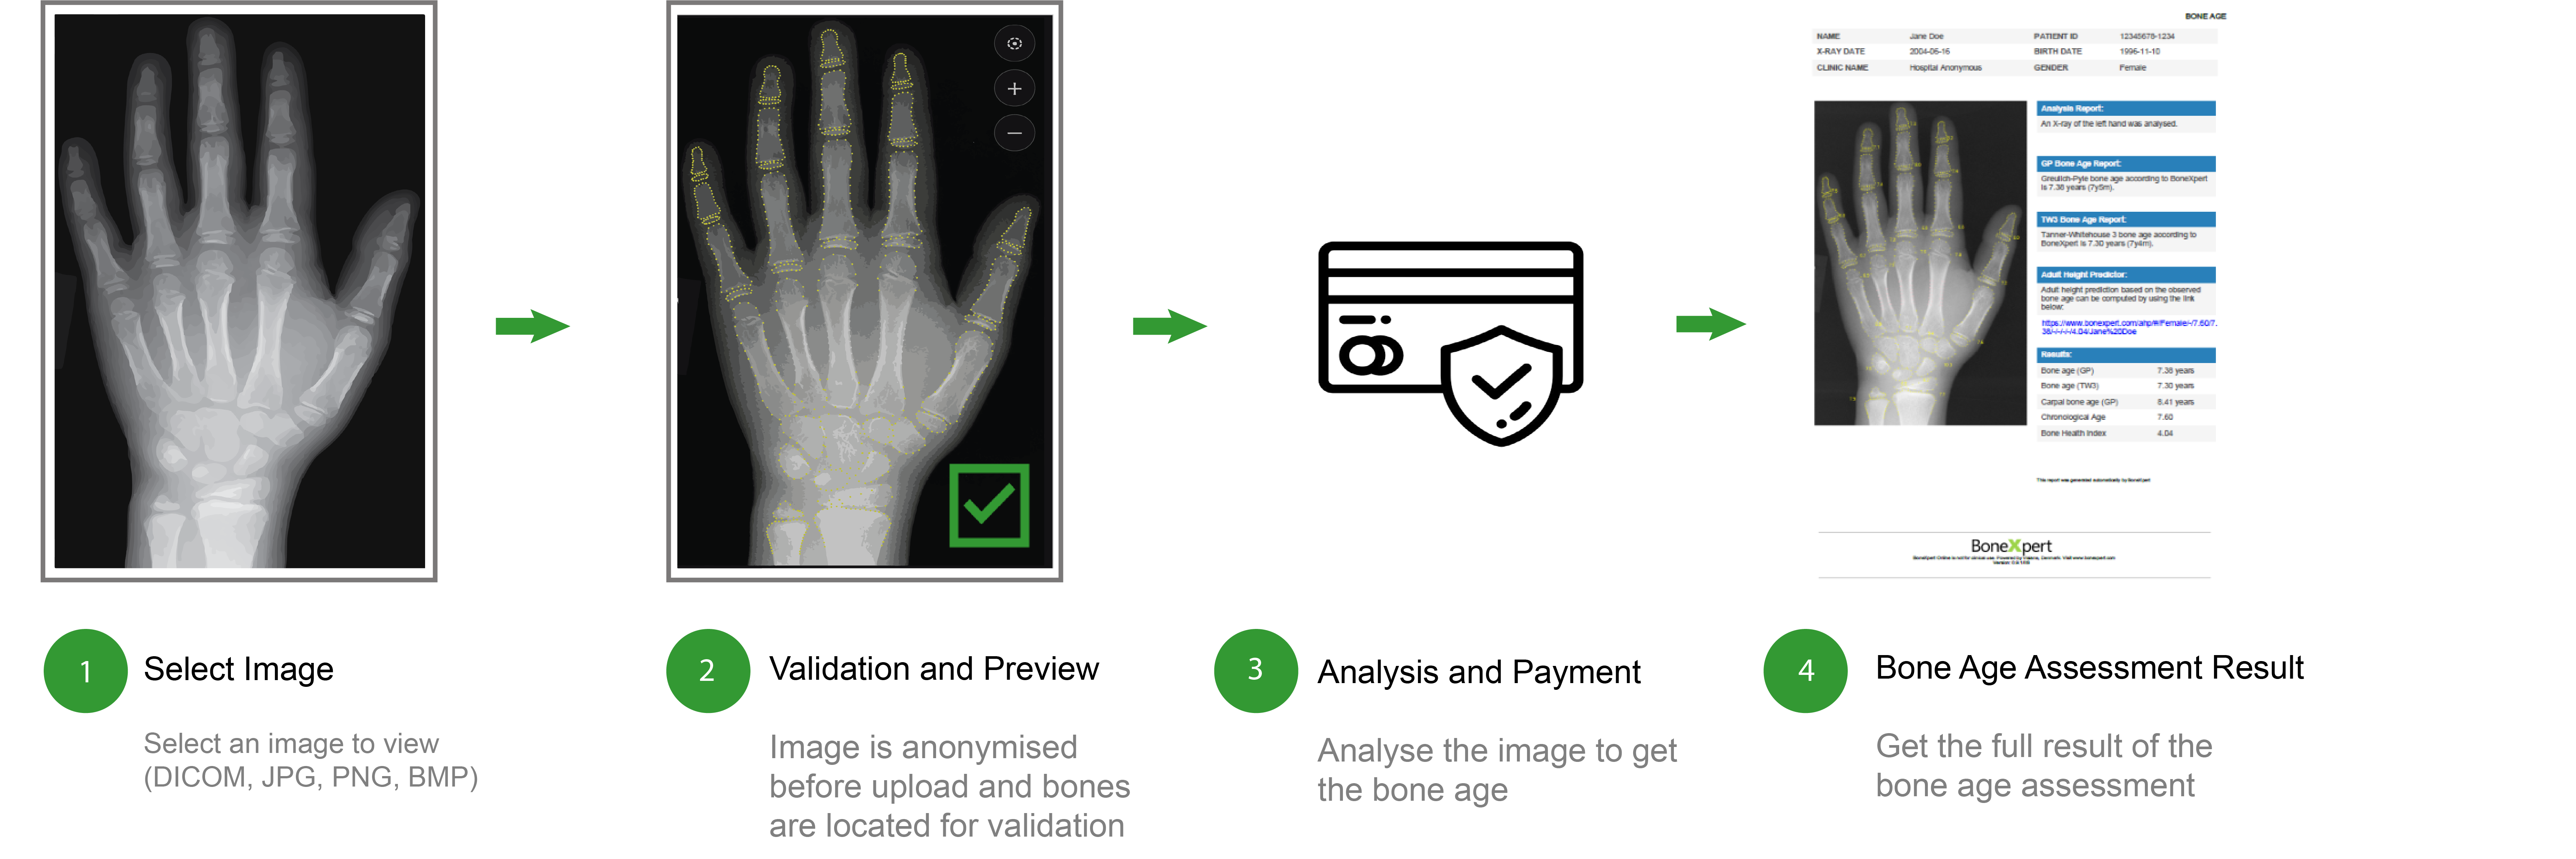

A single image can be analysed by dragging it into the browser or selecting it from computer files. Prior to bone age analysis on a BoneXpert Server, the hand image is anonymised. The user's personal information is securely stored on their computer, merging with the anonymised image once the payment is complete. An example of a completed analysis is provided below: